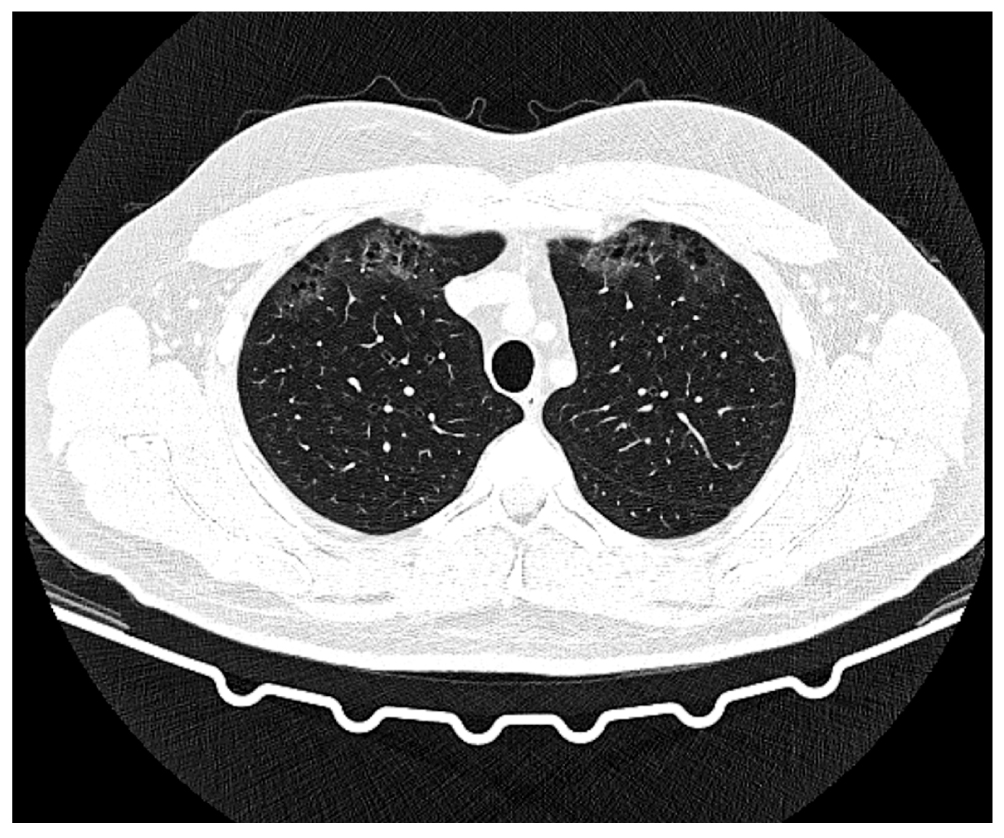

Fig. 4. Axial section, pulmonary window. Small bullae with ground glass areas. Day 16 of the disease, day 9 of hospitalization.

Fig. 5. Axial section, pulmonary window. Bilateral areas of low-intensity ground glass. Day 16 of the disease, day 9 of hospitalization.

Fig. 6. Axial section, pulmonary window. Thickened area in S8 of the right lung. Day 16 of the disease, day 9 of hospitalization.

Description of the chest CT scan dated August 2, 2022, on day 16 of the disease, day 9 of hospitalization (Fig. 4, 5, 6): The lungs are fully expanded. In subpleural sections S1, S3, and S5 of the right lung and S1/2 and S3 of the left lung, grouped small multi-row bullas together with areas of ground-glass type hypoventilation are observed. There are areas of heterogeneous infiltration, predominantly of low-intensity ground-glass type, in multiple foci of both lungs. In the subpleural sections of S8 of the right lung, dense consolidation is detected. The changes are not preferentially localized, with the greatest severity in the subpleural regions. Degrees of pathological changes in each lobe are as follows: right lung: upper lobe 20%, middle lobe 60%, lower lobe 40%–45%; left lung: upper lobe 15%–20%; lower lobe 25%–30%. The total lesion is thus 45%–50%.

Results: CT pattern of a bilateral infiltration, intermediate probability of viral etiology (CT2, 45%–50%); small bullas in both lungs. The effective equivalent dose is 1.908 m3v.